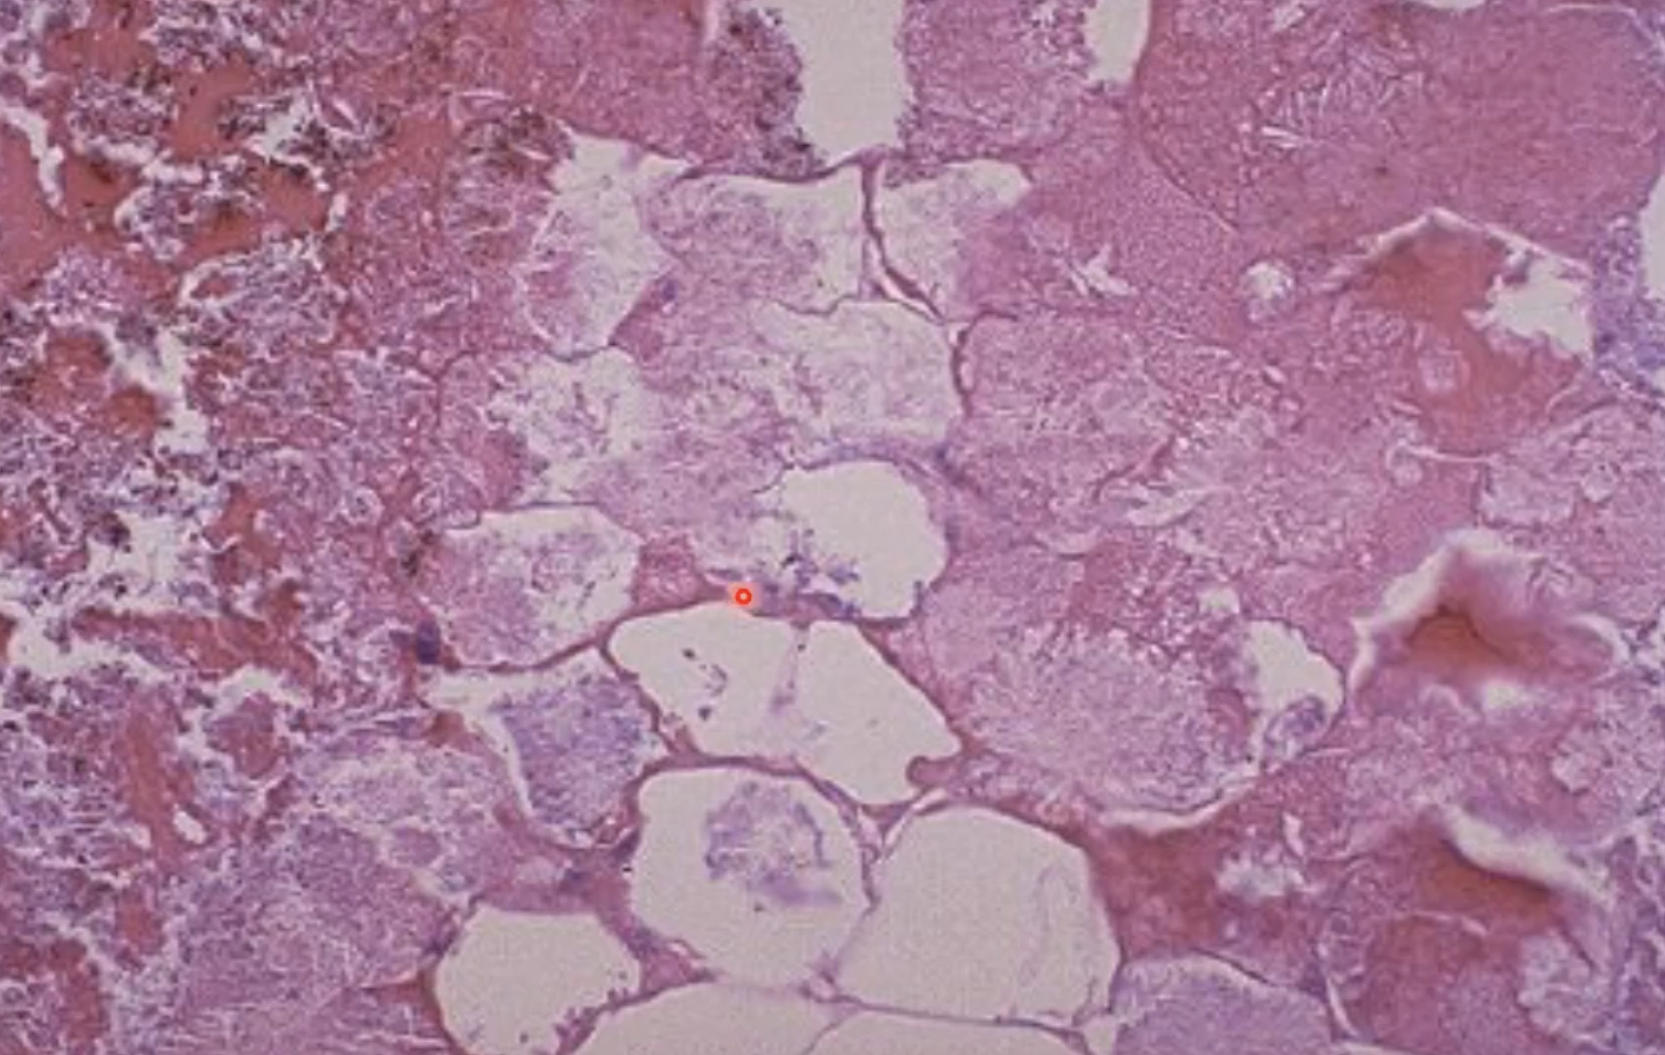

pancreatitis in dogs - fat necrosis; pancreas leaks lipase causing fat tissue necrosis - evidenced by the white tissue.

firm fat has turned into soapy mineralized material (like saponification) in cow - fat necrosis

adipocytes develop wispy blue material in fat necrosis